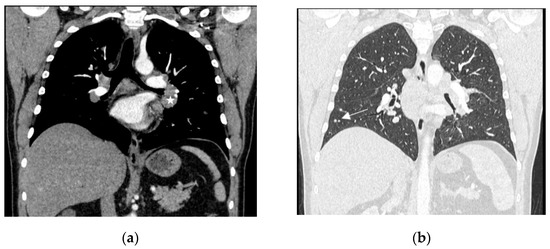

A 63-year-old man with a history of benign prostatic hyperplasia, an ex-smoker with a history of 15 pack-years, presented himself to the general practitioner due to sudden onset of severe chest pain, that radiated to his back, the interscapular region, and the lumbosacral area, as well as circumferential pain around the subcostal region. The pain did not respond to any painkillers. The patient reported weight loss of 12 kg in the past 6 months due to reduced appetite, but denied cough, dyspnoea, haemoptysis and fever. Physical examination did not reveal any significant abnormalities. Laboratory tests showed a slightly elevated erythrocyte sedimentation rate (ESR) of 40 mm/h (normal: 3–8 mm/h) and a CRP level of 36 mg/L (normal: <5 mg/L), but were otherwise within normal limits. ANA and RF were negative. A chest CT revealed multiple enlarged mediastinal and hilar lymph nodes (up to 44 × 21 mm in diameter), as well as a 10 mm nodule in segment 6 of the left lung. Abdominal and pelvic CT showed several hypodense, small (4–6 mm) focal lesions in the liver, which were nonspecific, and a few nonspecific hypodense areas of bone rarefaction up to 6 mm in size in the lumbar vertebrae. Histological examination of the mediastinal lymph node (group 7) obtained by EBUS-TBNA showed non-necrotizing granulomas and confirmed the diagnosis of sarcoidosis. To assess the disease extent, a positron emission tomography (PET)-CT scan was performed, which revealed numerous metabolically-active lymph nodes symmetrically distributed in the mediastinum and hilar regions, as well as a few metabolically active and inactive nodules in the lungs, which were most likely granulomatous in nature, but no metabolically active lesions were found in the abdominal organs or bones. An MRI of the thoracic and lumbar spine showed four nonspecific intramedullary foci in the L2 and L4 vertebral bodies, and the Th9 and Th11 thoracic vertebrae, which enhanced peripherally with contrast, and could represent either atypical hemangiomas or sarcoid granulomas, but their nature could not be definitively determined at that time (Figure 3). The patient was evaluated by a neurologist, who did not find any signs of brain or spinal cord damage, nor the cranial nerve or root involvement. Abdominal ultrasonography and ECHO were performed, and no abnormalities were detected. The parameters of the pulmonary function tests were normal. The serum calcium concentration and its daily excretion in urine were normal. Based on all the tests and clinical course, stage II sarcoidosis was diagnosed. Three weeks after the completion of the diagnostic workup, sudden loss of vision in the right eye occurred, and the patient was hospitalized in the ophthalmology department, where optic neuritis was diagnosed and intravenous methylprednisolone (1000 mg/day) for four days was initiated, followed by oral prednisone (60 mg/day). An MRI examination of the orbits confirmed the presence of lesions suggestive of optic neuritis (visual nerves with slightly uneven bilateral enhancement of the intraorbital parts, focal enhancement of the optic chiasm and left optic tract, and mild periorbital fat swelling of the right eye). No deviations were found in the MRI of the central nervous system (Figure 4). After steroid treatment was initiated, the patient regained vision, although there was still a limitation of the visual field in the right eye (which remained stable during further observation). He also reported a complete chest pain relief. In the follow-up MRI examination of the orbits, the periorbital fat swelling of the right eye subsided compared to the previous examination and there was no focal enhancement of the optic chiasm and left optic tract. In the follow-up MRI examination of the lumbar and thoracic spine, the two intramedullary foci in L2 and L5 decreased, the focus in Th11 regressed completely, and the one In Th9 remained stable—considering the dynamics of changes in vertebral bodies and response to the steroid treatment, involvement of bone marrow in sarcoidosis was confirmed. Prednisone treatment in tapered dose was continued for 2 years.

Three years after the termination of the steroid treatment, the patient began to complain of progressive weakness. A CT of the chest confirmed the disease progression in the lungs. Normocytic anemia, hypercalcemia and a decrease in the estimated glomerular filtration rate (eGFR) were found in laboratory tests. The parameters of the pulmonary function tests were normal as previously. Echocardiography did not reveal any features suggestive of cardiac sarcoidosis or significant pulmonary hypertension. The loss of visual field in the right eye remained stable—the patient remained under the care of the ophthalmologist. Based on the overall clinical-radiological picture and additional diagnostic tests, a relapse of sarcoidosis with hypercalcemia and renal impairment was diagnosed. Prednisone was re-initiated with a dose of 40 mg/day. After one week of treatment, serum calcium levels normalized. The prednisone dose was gradually reduced to 10 mg/day. Partial regression of diffuse and nodular changes was observed in radiological imaging, with a significant increase in eGFR and resolution of anemia in laboratory tests. Since the onset of illness, the patient denied respiratory symptoms, and pulmonary function tests did not show any ventilatory abnormalities.